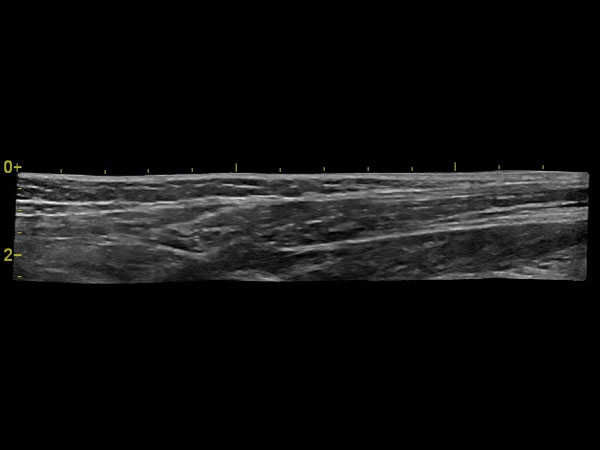

IMT (Intima Media thickness):

Да